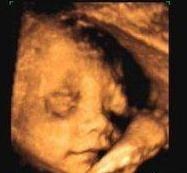

据黄晓明的工作人员透露,小明哥和baby之前早就检查过,胎儿的性别已经确定,是女孩,据说很多人都特别期待宝宝出生,因为这是检验父母颜值真假的唯一证据。不过据了解,胎儿出生以后,小明哥和baby可能不会公布相关照片,想要好好的保护孩子。